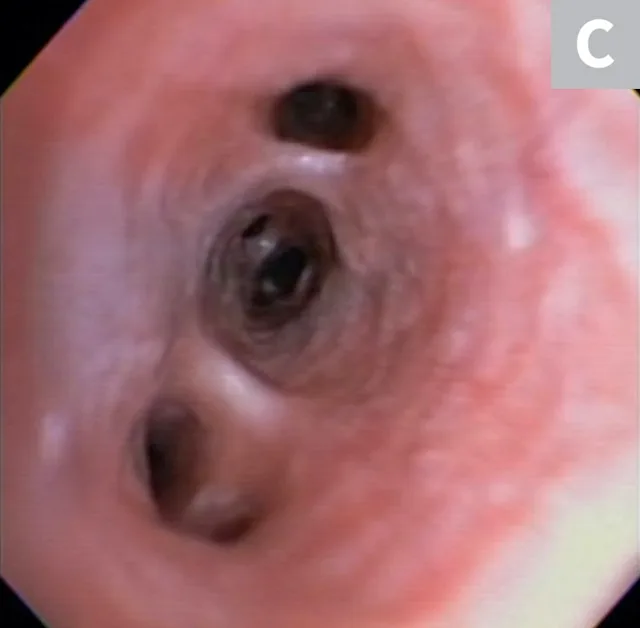

Serum chemistry profile and CBC results were normal, and heartworm antigen test results were negative. Thoracic radiography (right lateral, left lateral, ventrodorsal) revealed a diffuse bronchial pattern but was otherwise unremarkable with no cardiomegaly (vertebral left atrial size, 2.1 [normal, 1.4-2.2]; vertebral heart scale, 9 [normal, 8.7-10.7]) or observable airway collapse (Figure 1). Arterial blood gas showed partial pressure of arterial oxygen 97 mm Hg (normal, 81-103 mm Hg). Echocardiography revealed myxomatous mitral valve degeneration (B1) with no evidence of pulmonary hypertension.2 Laryngoscopy/bronchoscopy showed moderate mucosal irregularity and increased mucus of the lobar bronchi (Figure 2) with normal laryngeal function. Concurrent dynamic bronchial collapse of the left and right mainstem bronchi (grade II/III) was observed (Figure 3).3 Bronchoalveolar lavage was performed and submitted for cytologic evaluation and aerobic culture. Cytology revealed nonseptic neutrophilic inflammation (Figure 4); aerobic culture was negative.